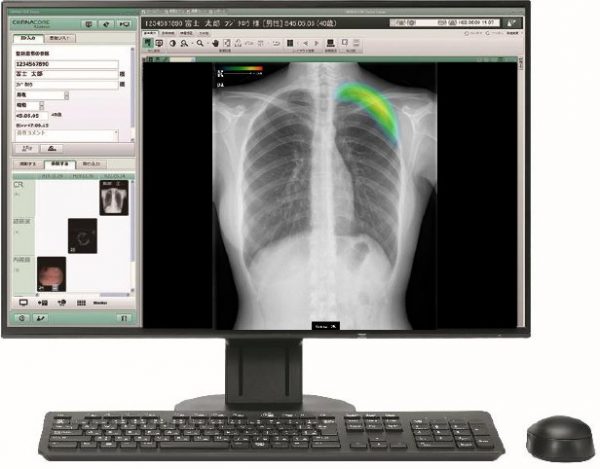

コンソール上で「CXR-AID」の解析結果を表示する。

③C@RNACORE+EX-Mobile

解析結果は、撮影した元画像と共に汎用画像保管診断装置(PACS)に転送が可能で、医師が画像診断ワークステーション上で診断を行う際に解析結果を補助情報として利用できる。当社のクリニック向け画像診断ワークステーション「C@RNACORE(カルナコア)」にも対応しており、クリニックの医師が「C@RNACORE」上で画像診断を行う際に、CXR-AIDの解析結果を参照することで、異常所見の見落とし防止を支援する。「C@RNACORE」に「EX-Mobile」を接続することで、DRカセッテのみならずCRシステム※5を含む汎用X線撮影装置で撮影した画像を解析することが可能だ。

C@RNACORE+EX-Mobileの使用イメージ

「CXR-AID」は、本年8月に発売したAI技術を活用して胸部単純X線画像から結節・腫瘤影、浸潤影、気胸の3つの画像所見を検出し医師の画像診断を支援するソフトウェアだ。結節・腫瘤影、浸潤影、気胸の候補領域を検出し、それらの異常領域の存在の可能性(確信度)を青から赤までのグラデーションカラーで表示。医師の見落とし防止を支援する。